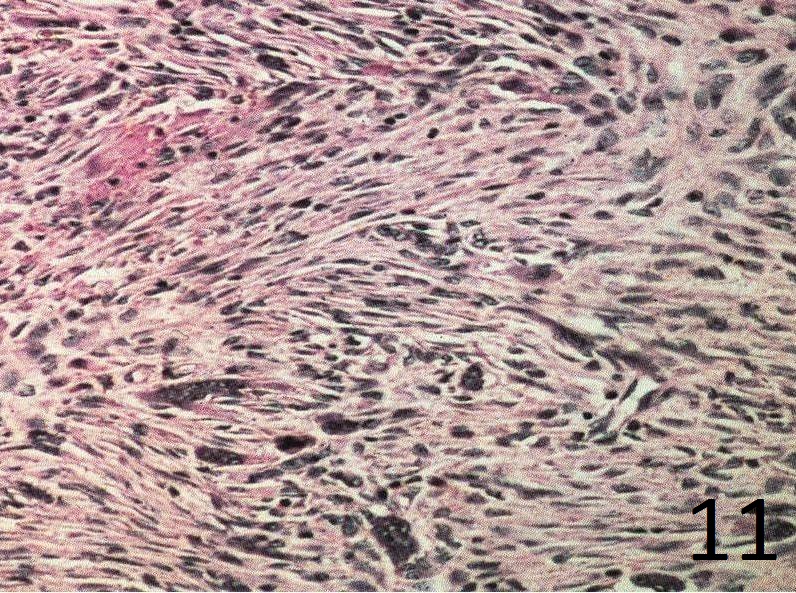

Microscopic

• Spindle cells are distributed in a storiform (swirling) pattern and mixed with other foci containing abundant histocytic cells (Fig. 10-11).

• Lipid laded histiocytes and macrophages

• Giant cells are present in irregular cluster

• Clusters of hemosiderin-iaden macrophages are dispersed

• The nuclei of the spindle cells and histocytes are regular

• Bland appearing cells with small uniform nuclei and no nuclear pleomorphism

Fig. 11

Fig.11: High power view of the lesion shows the storiform patern, bland spindle cells, fibrous tissue and hemosiderin laden macrophages.